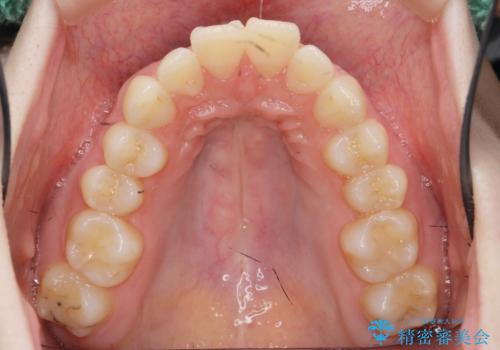

マウスピースで出っ歯感の改善

- 上の前歯が出ている感じを治したい、と矯正治療を希望され来院されました。

上顎歯列の突出感を改善すべくIPRを行い、下顎歯列を小さくすることで前歯の角度を大きく是正します、。

下顎歯列は元々前歯が1本少なく小さなアーチでしたが、下顎に合わせ上顎歯列もIPRを行い小さくすることで出っ歯感を大きく改善することが出来ました。